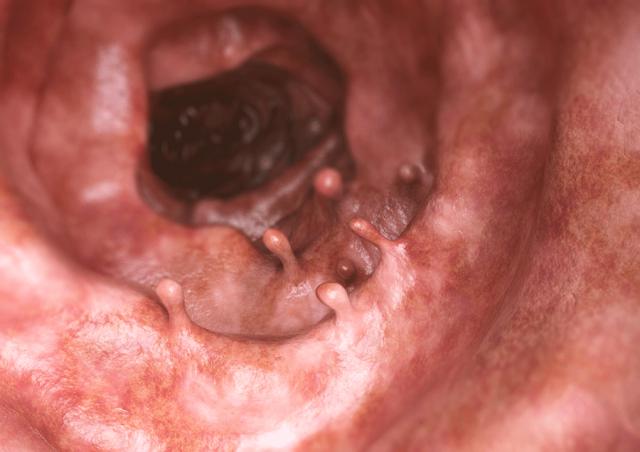

劉女士今年65歲,2年前在洛陽東大肛腸醫院腸鏡檢查中被發現腸道內有1cm左右大小的息肉,病理結果顯示為管狀腺瘤。但當時身體沒有其他不適癥狀,劉女士就不想折騰,沒有進行進一步的治療。

大約在一個月前,劉女士身上出現了異常的便血癥狀。女兒便又帶她到洛陽東大肛腸醫院進行檢查,經檢查發現劉女士腸道內存在多個息肉,最大的達到了3cm,病理活檢顯示為結腸癌。

洛陽東大肛腸醫院科普:什么樣的腸息肉會癌變

大部分息肉都是良性的,有少部分息肉有惡變風險。一般危險的息肉常以4種面孔出現:

① 超過2cm

腺瘤性腸息肉是公認的癌前病變,具有較高的癌變風險。

②腸壁上的息肉

這類息肉相較于普通息肉較難發現,也容易出現漏診,相對而言癌變的風險較高。臨床數據顯示,平坦型息肉只要超過1cm,即便是良性的也會在3年左右發展成進展期大腸癌。

③遺傳性息肉

這類息肉一旦出現,發生惡變的風險也會比普通的要高。

④ 多個息肉同時出現

腸道內出現息肉,數量越多的話癌變的風險也越高。